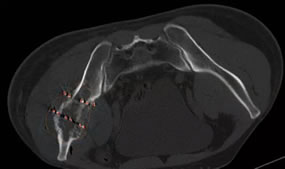

6月24日,我院介入科林征宇主任、陈锦主治医师及其团队成功开展福建省首例3D打印导向模板引导下的放射性粒子植入手术。此患者为男性,40岁,肝癌术后1年余,发现左髂骨转癌半年,行外放疗+索拉非尼靶向治疗后肿瘤残留,症状表现为左髋部疼痛,站立及行走时明显,影响日常生活及睡眠。根据患者术前的CT图像,医疗团队在PROWESS TPS软件中确定肿瘤的大小、位置及与危及器官的毗邻关系,利用计算机模拟设计一个与体表完全吻合的模板,并在模板上设计出植入粒子的“针道”,按照瘤体照射剂量的TPS计划设计每个“针道”的深度、角度及植入粒子的数目,精心的术前准备使得术后结果与术前计划高度吻合,做到了更加便捷、精准、微创,使瘤体局部放射学剂量最优化。

术前设计进针路线和粒子规划 术后对比DVH放射剂量分布均匀